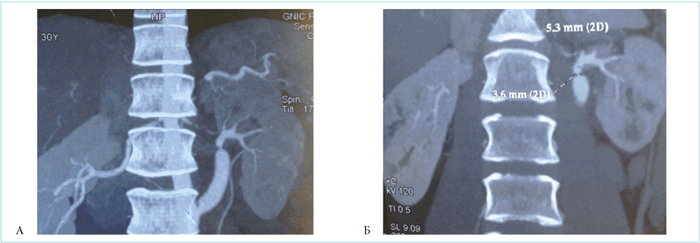

Пациентке была выполнена МСКТ-ангиография брюшной аорты и висцеральных артерий с введением контрастного вещества, по результатам которого выявлен гемодинамически незначимый стеноз шунтированной артерии в проксимальном отделе, значимый стеноз в дистальном отделе левой почечной артерии — по дистальному краю шунта (рис. 1).

Рисунок 1. А. Стеноз левой почечной артерии сразу после шунта. Б. Диаметр почечной артерии в месте стенозирования (3,6 мм) и после стеноза (5,3 мм)

Picture 1. A. Left renal artery stenosis, immediately after angioplasty. Б. Diameter of the renal artery at the stenosis site (3.6 mm) and after stenosis (5.3 mm)